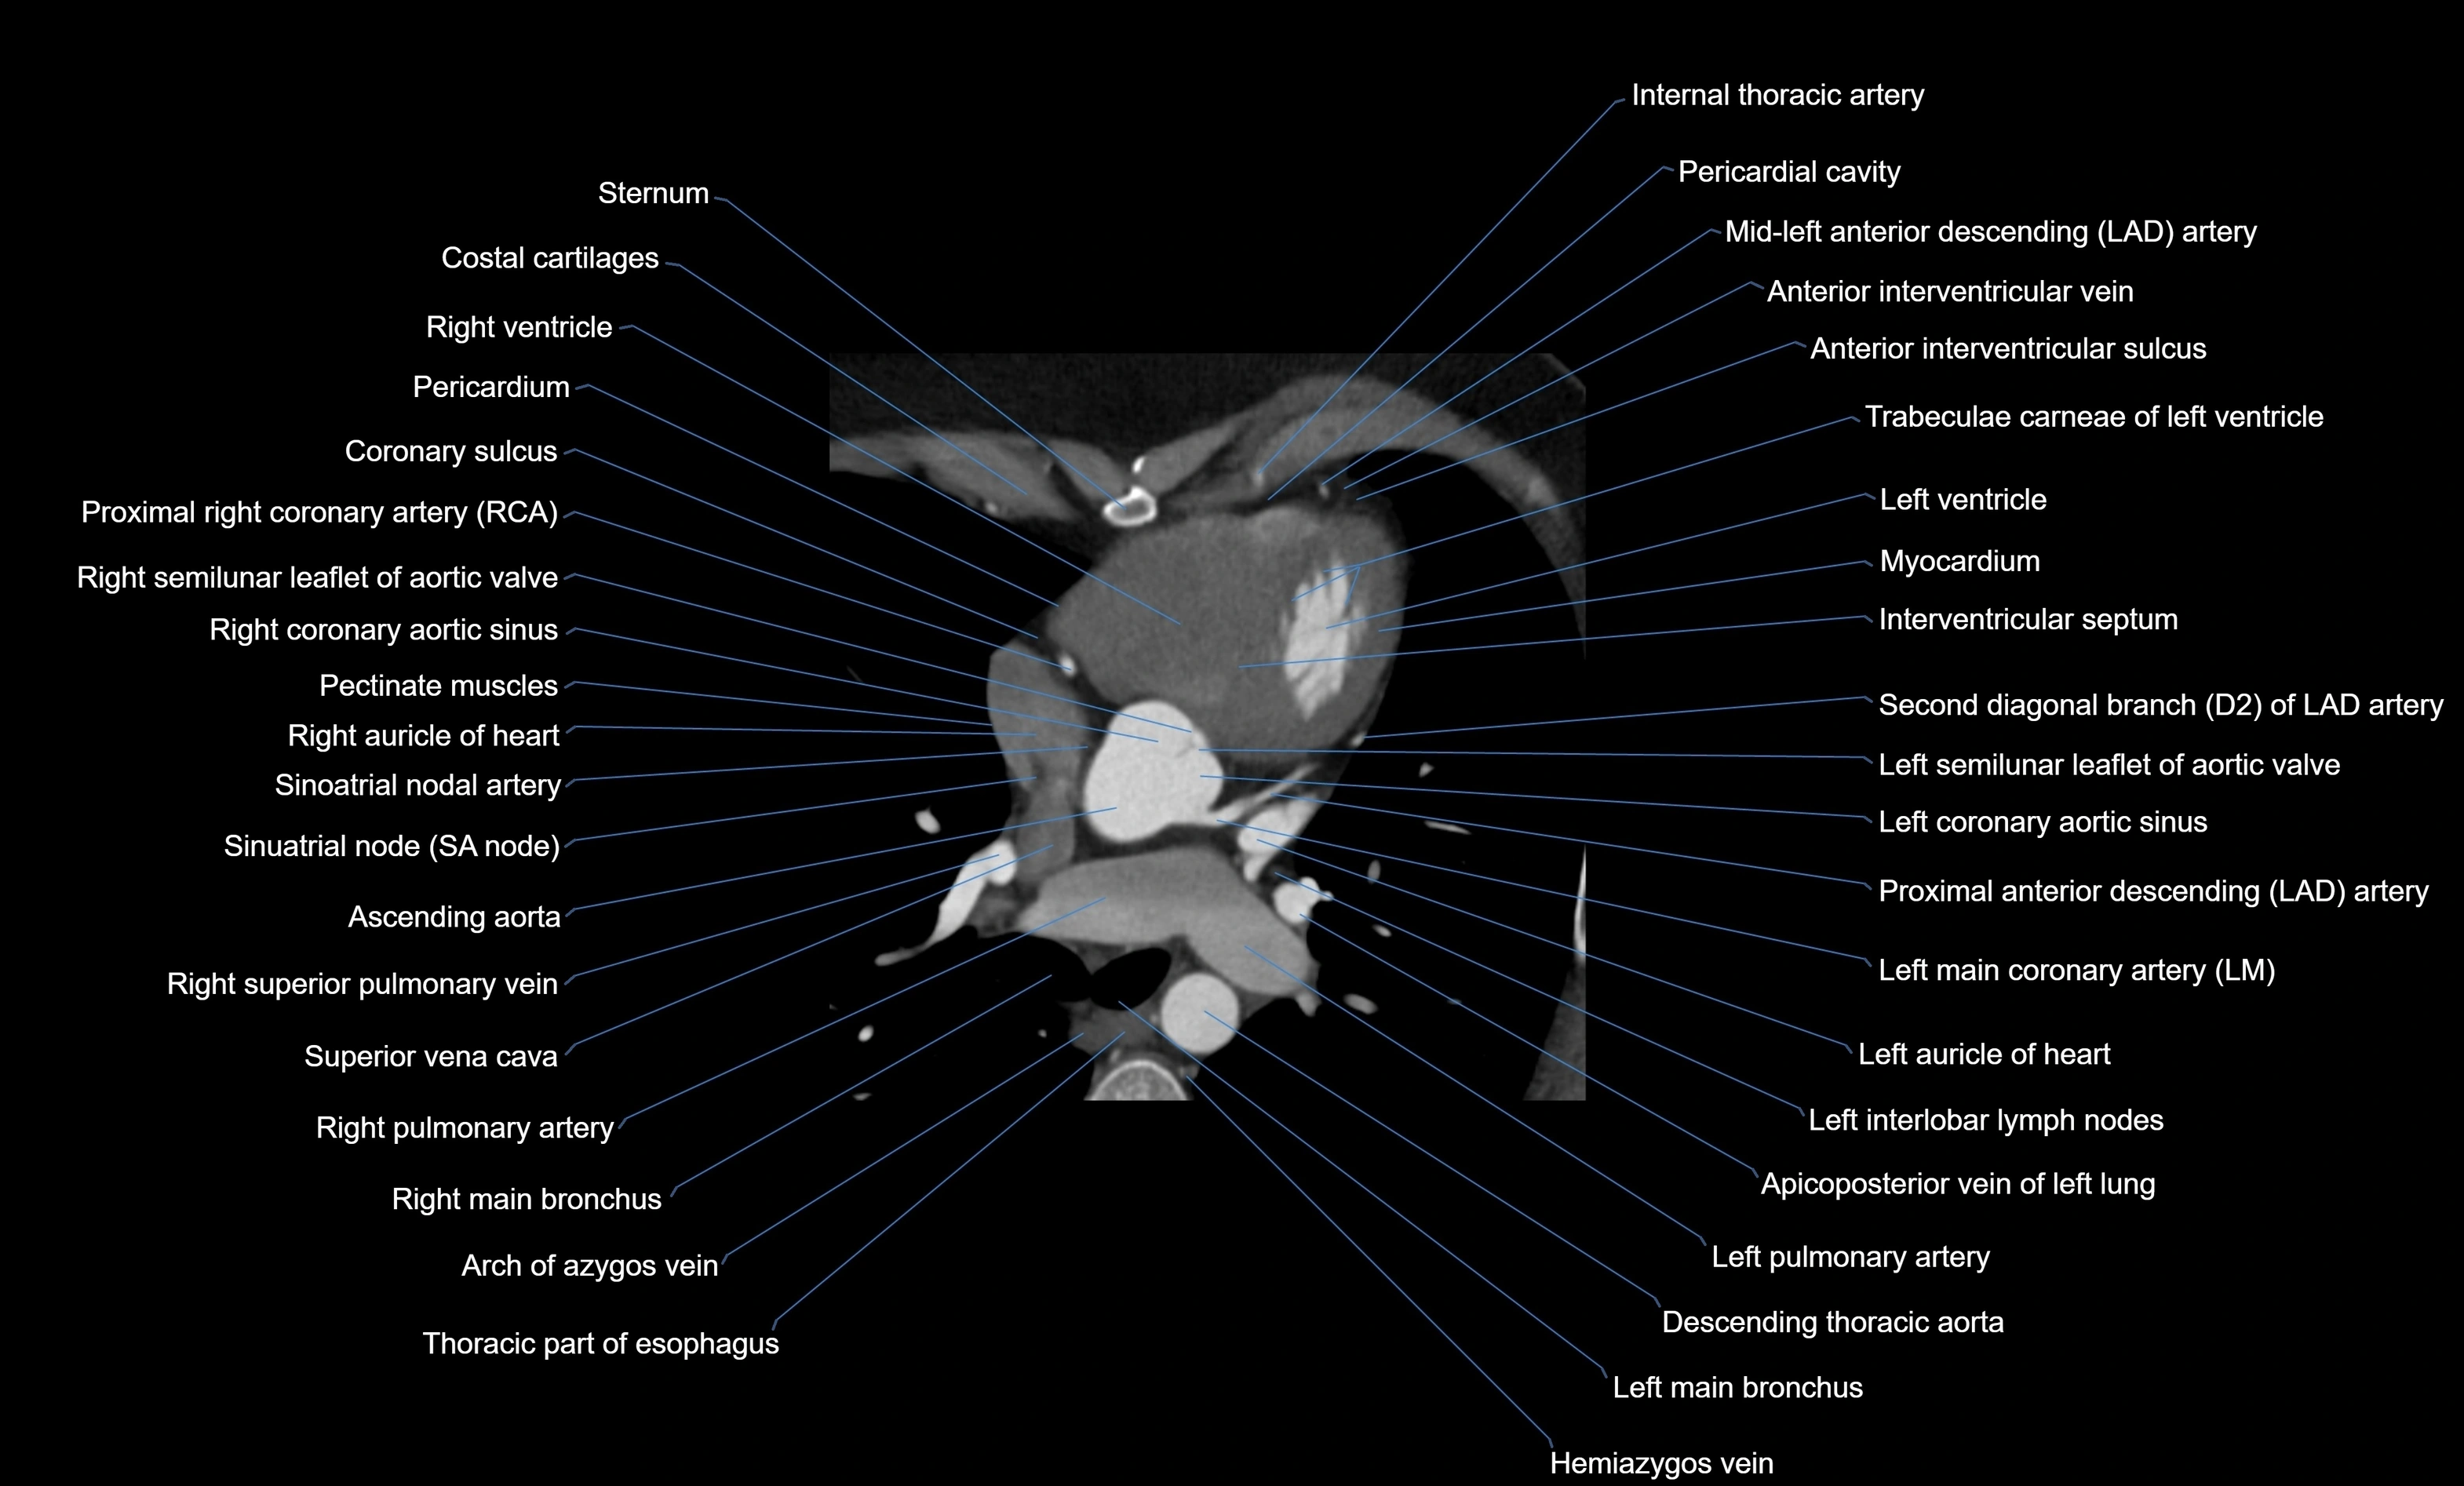

CT images